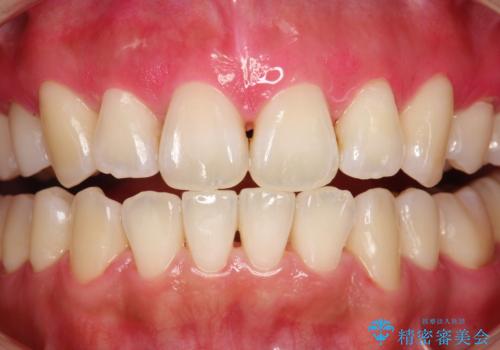

染め出しをしての歯磨き指導とPMTC

- 定期的にメンテナンスにいらしている方です。日々の歯磨きチェックもかねて染め出しとPMTC30分コースを行いました。